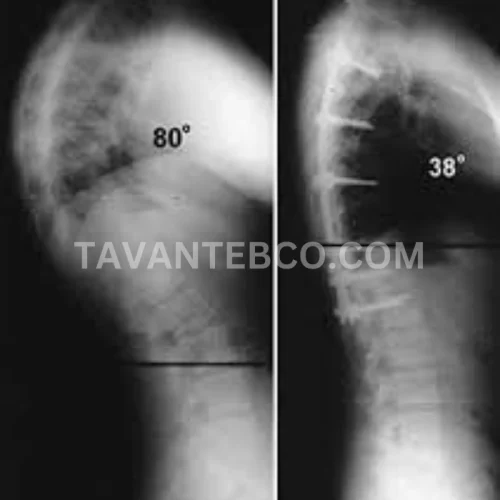

در موارد شدید کایفوز که زاویه انحنا بیش از ۷۰ درجه باشد یا همراه با مشکلات جدی مانند درد مداوم، فشار روی اعصاب، اختلالات تنفسی و محدودیت شدید حرکتی باشد، معمولاً جراحی بهعنوان گزینه درمانی در نظر گرفته میشود. در این روش با استفاده از پیچها و میلههای مخصوص، ستون فقرات در وضعیت مناسبتر تثبیت میگردد. جراحی بیشتر برای موارد پیشرفته توصیه میشود و نیازمند مراقبت و توانبخشی پس از عمل است.

درمان غیرجراحی با بریس اصلاحی هوشمند و سهبعدی در سال ۱۴۰۴ به عنوان یکی از مؤثرترین روشها شناخته شده است. این بریسها بر اساس اسکن بدن طراحی میشوند و کمک میکنند بدون نیاز به جراحی، زاویه قوز کاهش یافته و فرم طبیعی ستون فقرات حفظ شود.